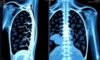

Гемолитическая анемия — это состояние, при котором происходит разрушение эритроцитов (красных кровяных клеток) в организме быстрее, чем они могут быть восстановлены. Эритроциты играют ключевую роль в доставке кислорода к тканям и органам, и их недостаток может вызывать различные проблемы со здоровьем. Представьте себе, как ваш автомобиль теряет мощность, если в двигателе недостаточно топлива. То же самое можно сказать и о вашем организме, когда уровень эритроцитов снижается.

Есть несколько типов гемолитической анемии, и каждый из них имеет свои особенности. Чтобы лучше разобраться с этим состоянием, давайте кратко рассмотрим, как именно происходит разрушение красных кровяных клеток и какие факторы могут влиять на этот процесс.